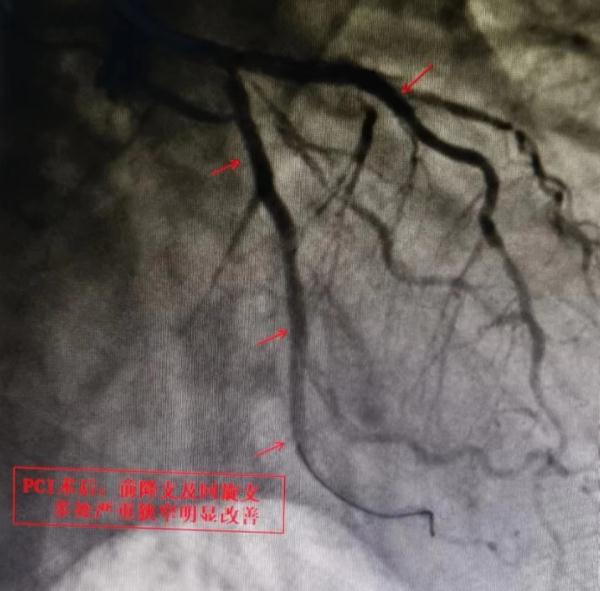

接诊的心内五病区主任容志毅在详细询问病史后,高度怀疑欧爷爷有心脏血管方面的疾病。入院后,经冠状动脉造影结果显示,患者心脏多支主要血管严重病变,左前降支、左回旋支皆有75%以上的弥漫性狭窄,严重狭窄处达95%。原来困扰欧阳爷爷半年之久的“胃病”竟然是“心病”。

△术前术后影像对比

在经过商讨后,容志毅主任医疗团队决定为患者实施介入微创手术。术中,手术团队通过给予心脏支架“搭桥”,开通狭窄血管,多处心脏堵塞血管实现了“再通车”,手术顺利完成。术后,欧爷爷打嗝嗳气的症状完全消失。目前,患者已顺利出院,回家休养。